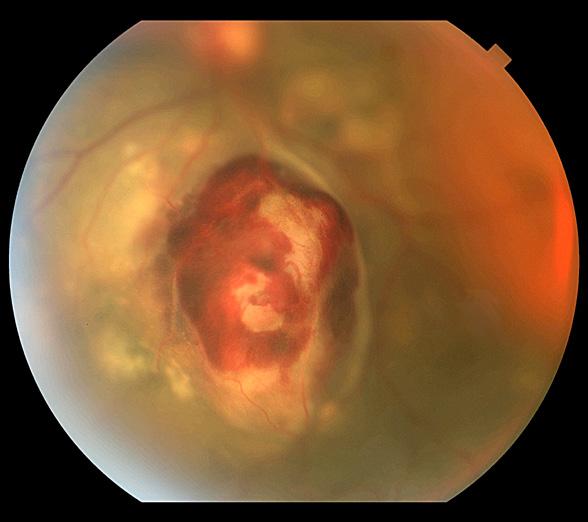

Fundus Photography High Magnification 20° Papilledema

Meghan Menzel, CRA

University of Iowa Hospitals and Clinics Iowa City, Iowa